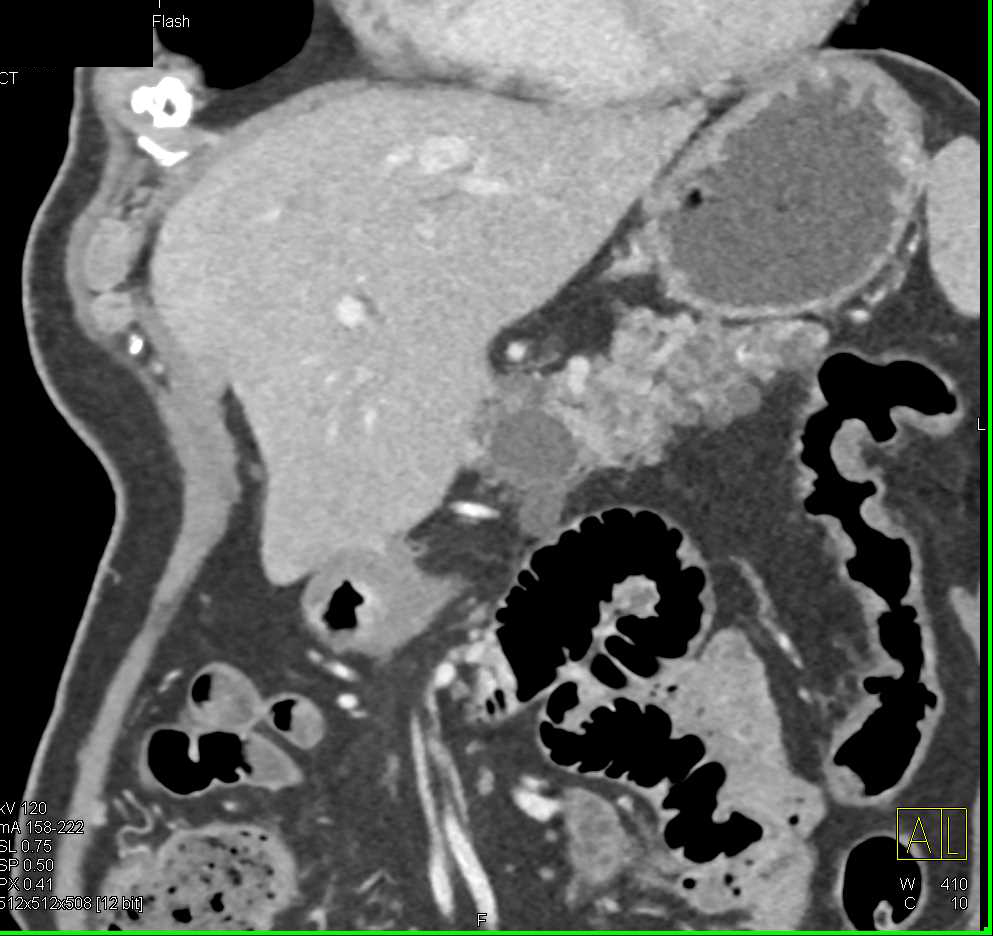

Neuroendocrine Tumor Pancreas Metastatic to the Liver